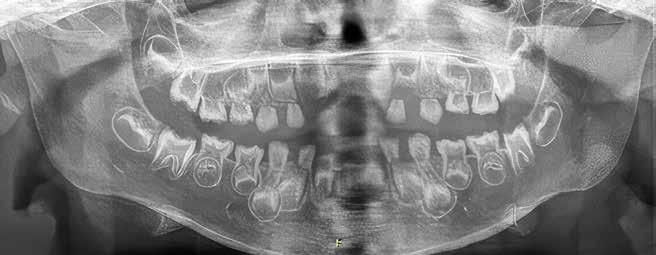

Udbyttet af disse nordiske fællesmøder kan vise sig i så konkrete tilfælde som et patienttilfælde med en udiagnosticeret otteårig pige, født med mitralklapinsufficiens, lav legemshøjde (-2 SD) og dysplastiske tænder med frembrudsproblemer og spontane nekroser til følge. Casen fremlægges på et møde, hvor to af deltagerne mener at have set lignende (Fig. 1A, B). Efter endt møde fremsendes yderligere information fra Aarhus med opfordring til, at der kunne være en mutation i LTBP3-genet, også

Panoramarøntgen 4 og 7 år

Fig. 1. A. 4-årig pige ved henvisning. Primære incisiver mistet på grund af spontane nekroser. Primære og permanente tænder ses dysplastiske og stort set uden emalje. B. Nu som 7-årig. 6’erne er endnu ikke frembrudt, men ses resorberede under slimhindedække. Der ses pulpaoverkapninger og endodontisk behandling af 1+, som har virket efter hensigten og bevaret tænderne i fronten. Endodontisk behandling på yderligere et antal tænder må forudses.

Fig. 1. A. 4-year-girl at the time of referral. Primary incisors have been lost because of spontaneous necrosis. Both permanent and primary dentition is without enamel and with dysplastic morphology. B. Same girl as 7-year-old. Molars are still not erupted but are seen to be resorbed preerupted. There has been done endodontic treatment in several teeth in the front, which has given function for now. It must be taken into account that more teeth will need endodontic treatment in the future.

kaldt DASS (Dental Anomaly and Short Stature). Efter yderligere henvisning til afdeling for klinisk genetik finder man en sygdomsfremkaldende variant i netop det gen (4). Pigen kan nu gå i relevant kardiologisk opfølgning og på sigt blive tilbudt relevant genetisk rådgivning og eventuelt prænatal diagnostik, når hun en dag selv ønsker at få børn. Ud over dette blev tandbehandlingen også drøftet i det nordiske forum. Patienten har siden tandfrembrud fået foretaget enkelte profylaktiske pulpaoverkapninger

og forseglinger af kronerne for at forebygge spontane nekroser. Dette gøres for at sikre tændernes bevarelse under væksten. På sigt forventes tænderne at mistes og erstattet implantatprotetisk, når dette findes relevant. Samtlige behandlinger er varetaget i højspecialiseret regi, men patienten følges også i primærsektoren, hvor samarbejdet mellem netop hospitalsbehandlingerne og kommunal tandpleje findes af stor betydning.